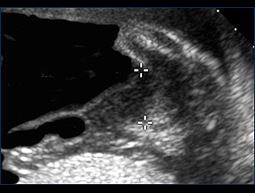

After successful treatment, the donor bladder begins to fill (small black circle in the middle of the abdomen) and the blood flow in the umbilical cord improves (right image).